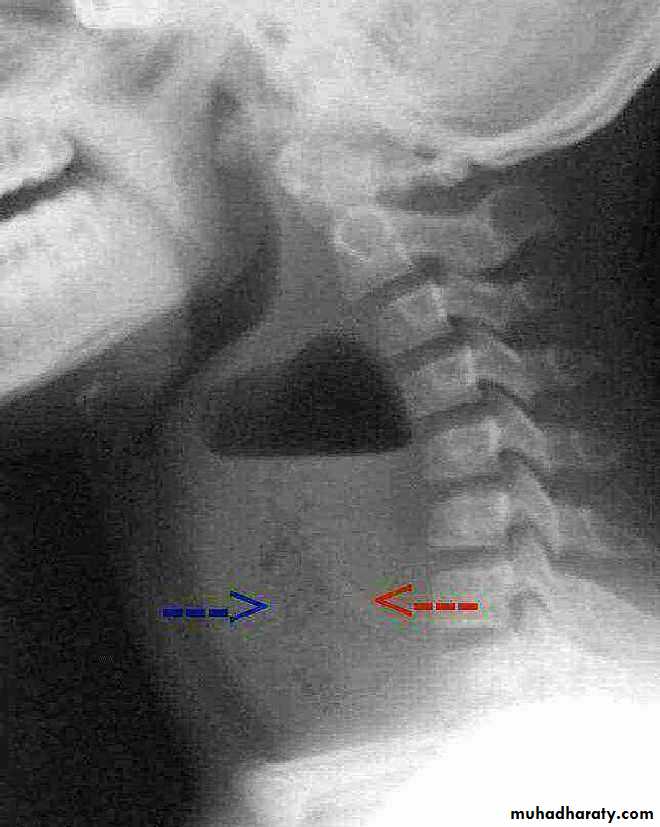

Orange arrow pharynx pushed anteriorly

22.Retrophyrengeal abscess

CT scan (scanogram) ,lateral view of the neck shows: Widening of retropharyngeal space with air fluid levelthymus gland in neonate